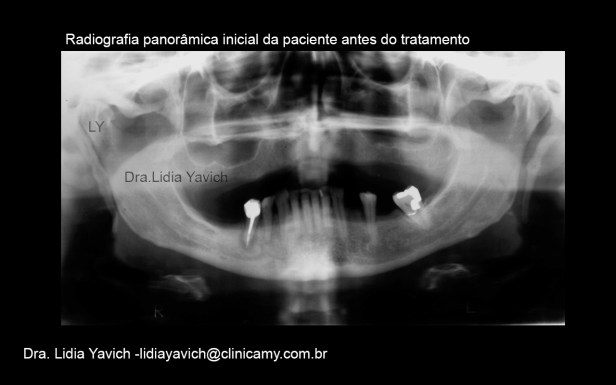

Radiografia panorâmica da paciente:

Reabsorção alveolar horizontal generalizada.

Desgastes dentários (atrição): dentes anteriores.

Côndilos mandibulares assimétricos e imagem sugestiva de osteófitos em ambas as cabeças mandibulares.

Calcificação do ligamento estilo mandibular bilateralmente.

Processo periapical no elemento tratado endodonticamente.